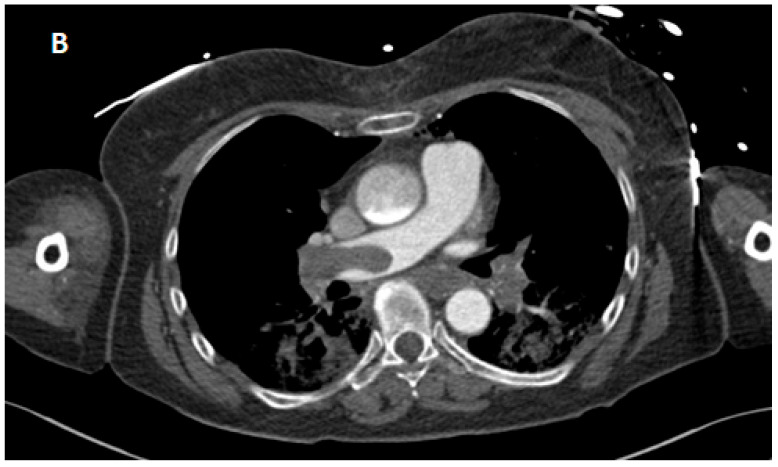

Background and Clinical Significance: Fulminant pulmonary embolism (PE) leading to an out-of-hospital cardiac arrest (OHCA) is associated with a high mortality rate and cardiopulmonary resuscitation (CPR) frequently failing to achieve return of spontaneous circulation (ROSC). Extracorporeal CPR (eCPR) has emerged as a potential life-saving intervention. Case Presentation: A 66-year-old woman suffered an OHCA due to massive PE, presenting with pulseless electrical activity (PEA). After 90 min of pre- and in-hospital CPR without sustained ROSC, venoarterial extracorporeal membrane oxygenation (va-ECMO) was initiated as eCPR upon arrival at the hospital. Even after implantation of the va-ECMO, there was initially a pronounced acidosis (pH 6.9) with a high elevated lactate level (>30 mmol/L); these factors, together with the prolonged low-flow period, indicated a poor prognosis. Further diagnostic tests revealed intracranial hemorrhage (subdural hematoma), and systemic lysis was not possible. With persistent right heart failure, surgical thrombectomy was performed during hospitalization. Intensive multidisciplinary management finally led to successful therapy and weaning from mechanical ventilation, as well as to complete neurological recovery (CPC-Score 1-2). Conclusions: This case illustrates that eCPR can facilitate survival with good favorable neurological outcomes despite initially poor prognostic predictors. It underscores the importance of refining patient selection criteria and optimizing management strategies for eCPR in refractory cardiac arrest secondary to PE.